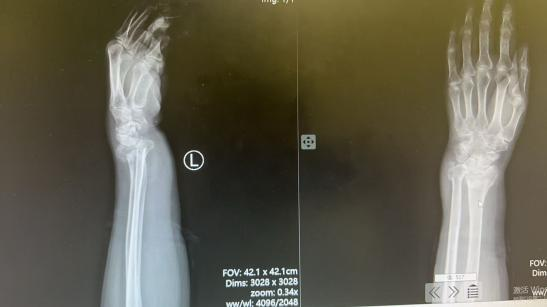

接诊医师薛安邦第一时间为杨奶奶开展详细查体,结合X线影像学检查,明确诊断其为左尺骨远端合并桡骨远端粉碎性骨折,骨折端移位明显,伤情复杂棘手。考虑到患者年事已高,手术治疗不仅面临麻醉风险,术后恢复周期长、并发症发生率也会显著增高,杨奶奶及家属在知晓手术相关风险后,明确提出拒绝手术、希望采取保守治疗的诉求。

复位完成后,复查X线片显示,患者骨折端对位对线良好,完全达到临床治疗预期,杨奶奶的腕部疼痛也得到明显缓解,整个诊疗过程顺利高效。“本以为老人年纪大了,骨折这么严重肯定要开刀,没想到薛医生几下手法复位就解决了问题,老人少受了大罪,太感谢红会医院的医生了!”杨奶奶的家属对治疗效果赞不绝口,连连向手法复位室团队表达谢意。